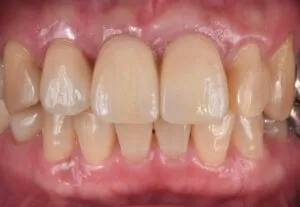

治療内容:前歯2本のラミネートベニア治療

治療費用¥88,000×2(税込み)

リスク:噛み合わせにより欠けることがあります

治療期間:1.5ヶ月